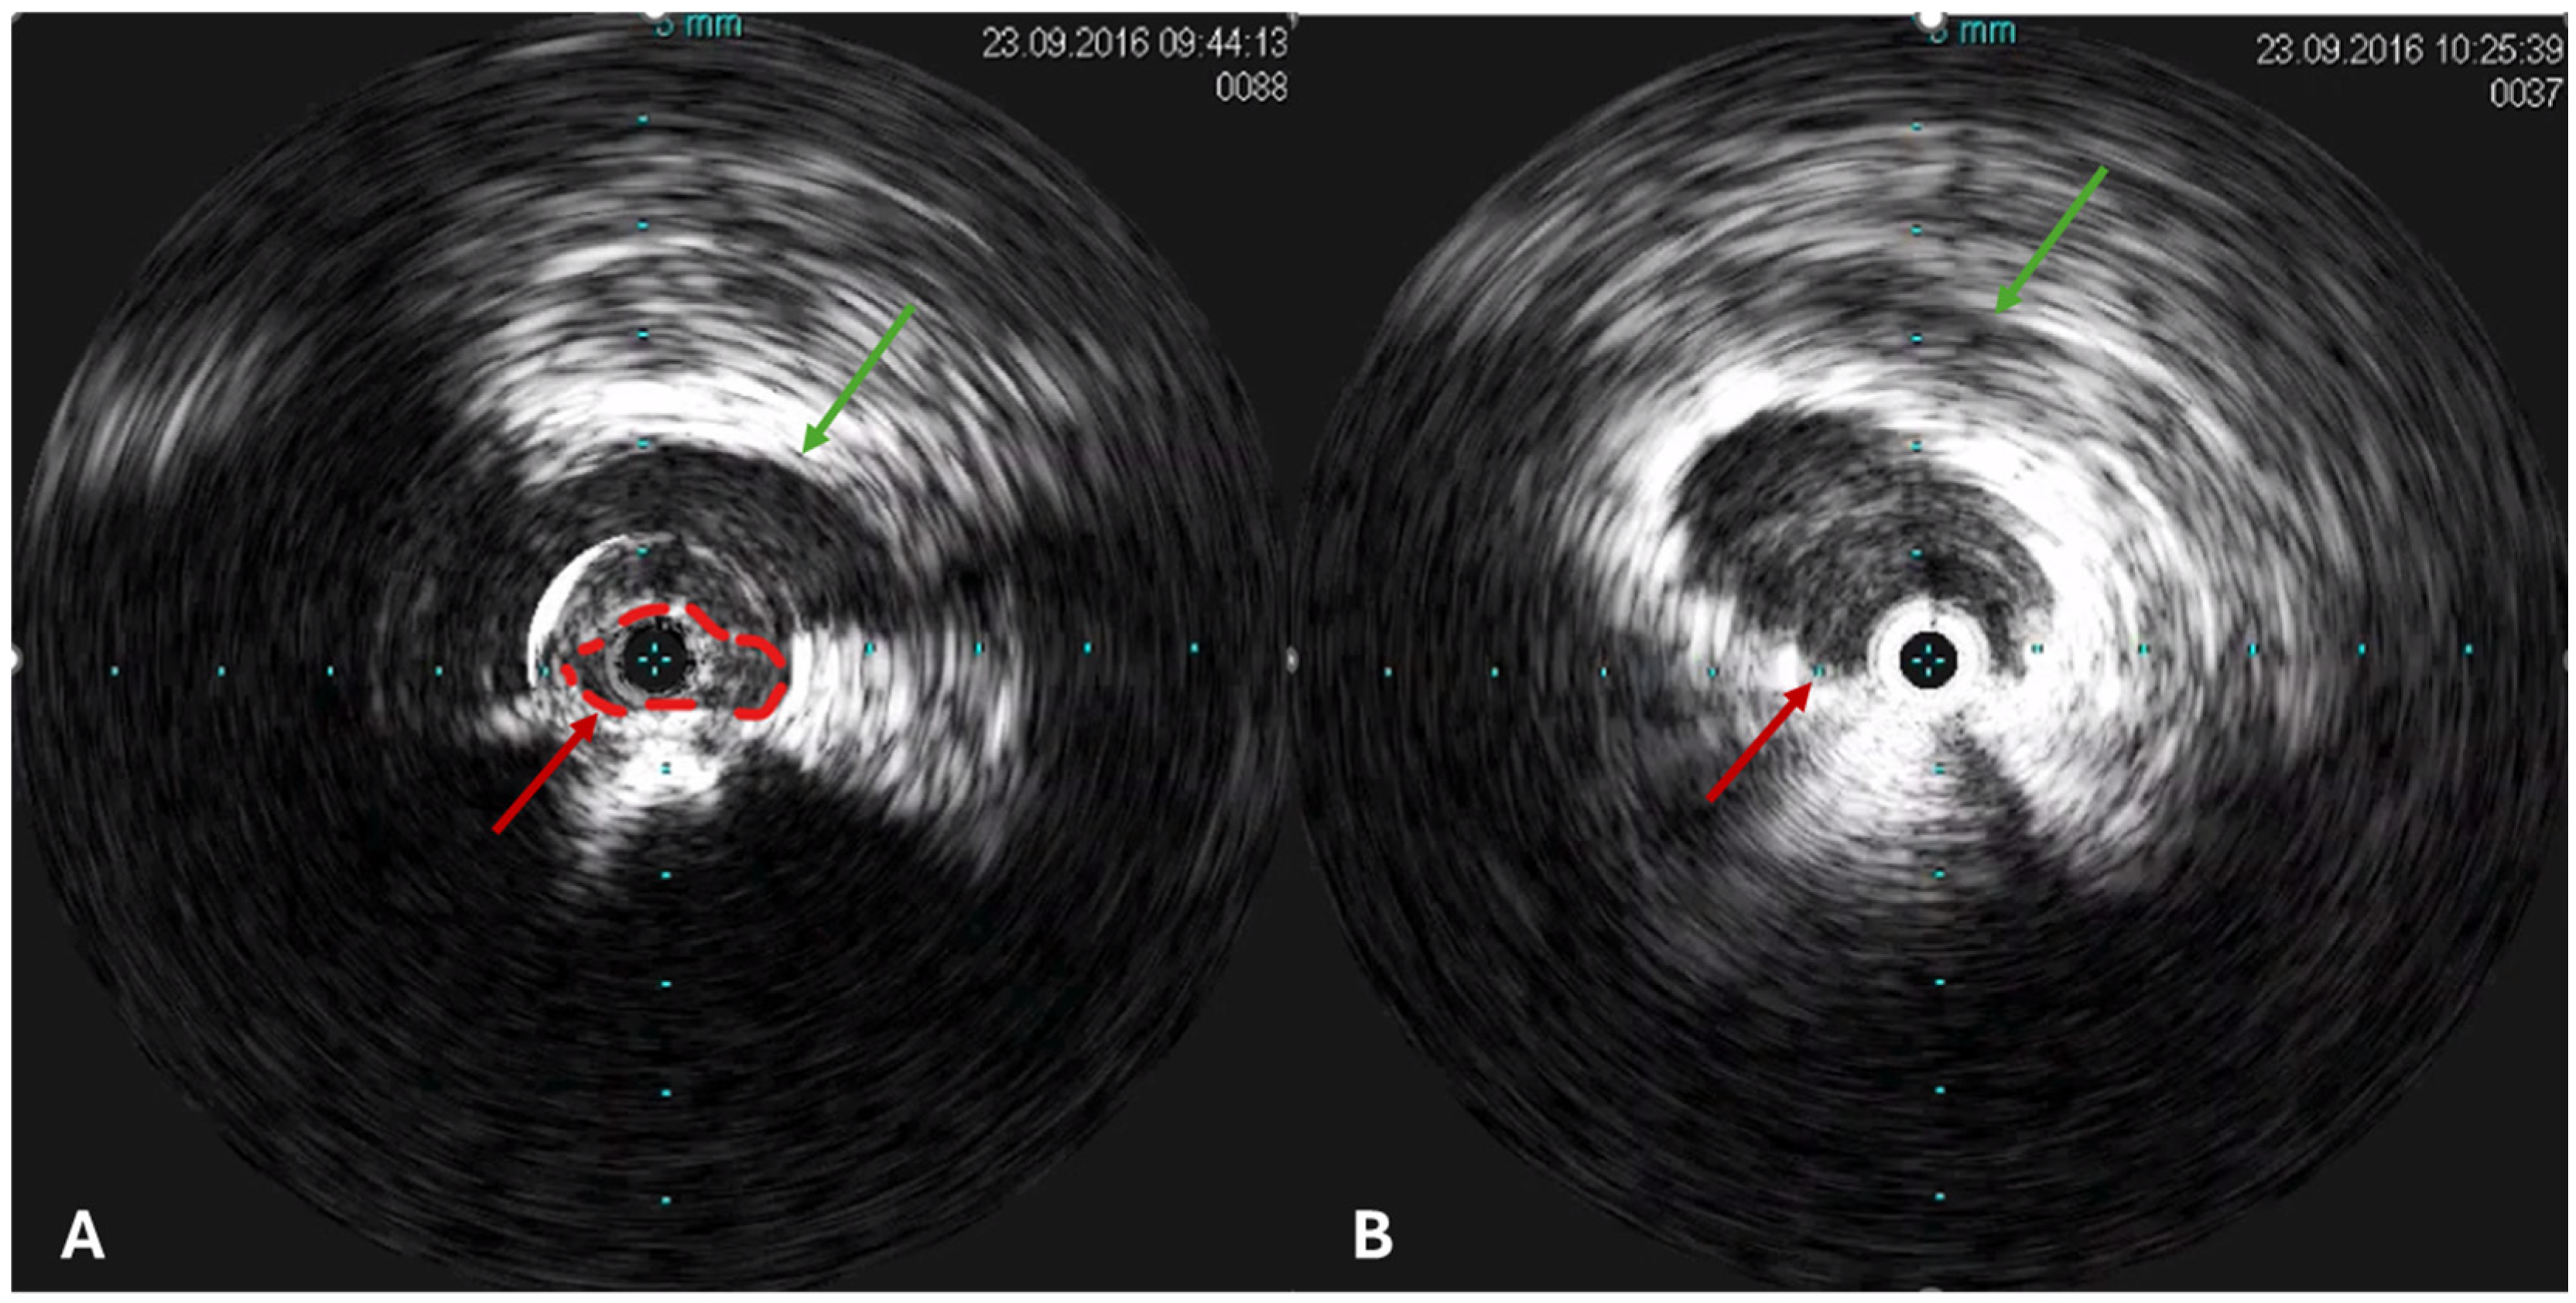

2.3.2. Catheter Venography and Intravascular Ultrasound